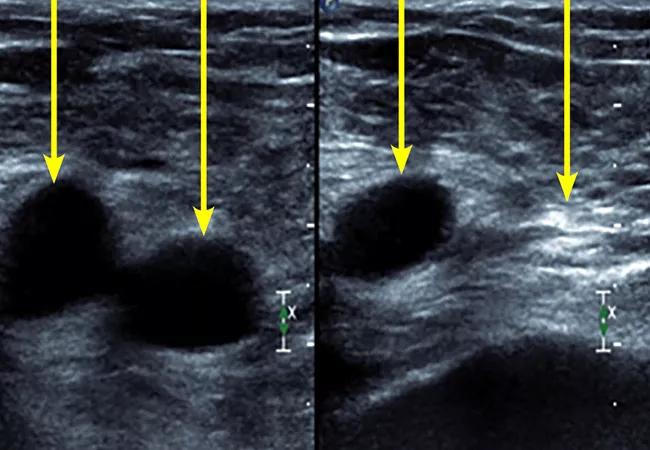

Duplex ultrasonography can show evidence of deep vein thrombosis if a venous segment is not compressible (Figure 3). Of note, approximately 70% of patients with pulmonary embolism have evidence of deep vein thrombosis on imaging studies.4

Figure 3. Example of lower-extremity duplex ultrasonography. Arteries and veins are labeled. Veins without deep vein thrombosis are compressible, as seen on the left. A vein is shown that is not compressible, suggesting deep vein thrombosis.